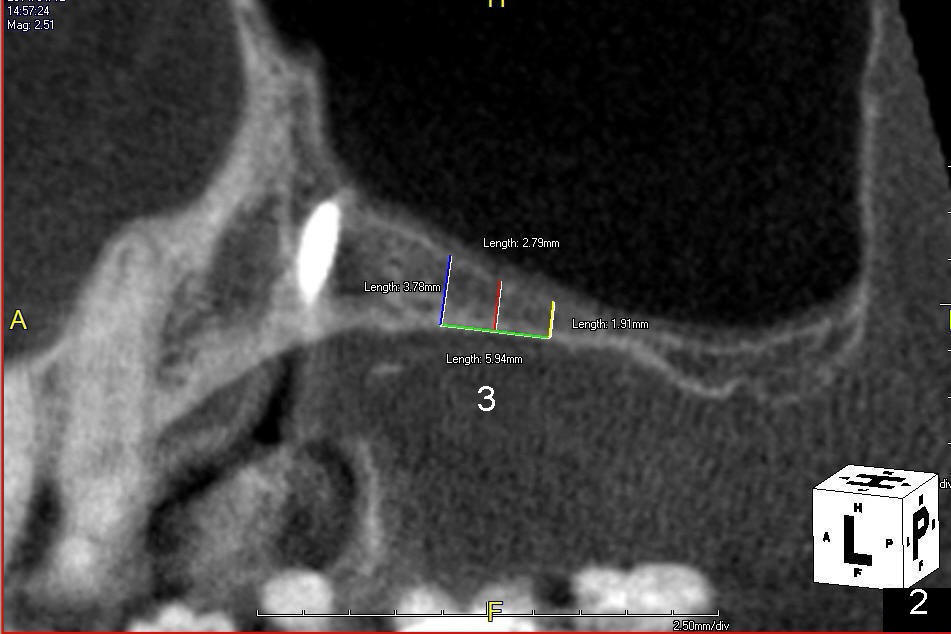

A 56-year-old lady lives out of state. She requests implant treatment for the upper right quadrants. Implants were removed by her previous care provider due to pain and infection. The premolars (Fig.1: #4,5) are provisionalized with a mini-implant (*). CBCT scans (Fig.1,2 (sagittal sections); Fig.3-6 (coronal section) show limited bone height involving the sites of the teeth #2 (Fig.1,3), 3 (Fig.2,4) and 4 (Fig.1,5). The buccolingual width is narrow at the sites of the teeth #4 and 5 (Fig.5,6).